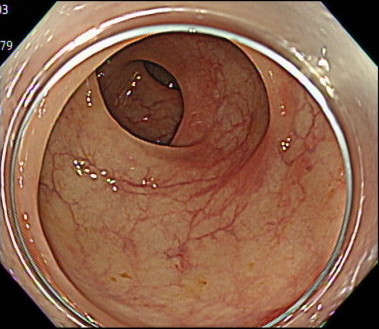

7. 先端フードを使用しないことで、広い視野を実現

「どんなに小さなポリープや変化も見逃さない」

大腸カメラでは、「先端フード」とよばれるカメラの先端につけるキャップのようなものがあります。

このキャップを内視鏡に装着することで、カメラの挿入がしやすくなるというメリットがあります。

しかし、周りの視野がせまくなるというデメリットがあります。

当クリニックでは、「軸保持短縮法」により腸に負担なくスムーズな挿入を行うことで、先端アタッチメントなしでの大腸カメラ検査を実現しています。

これにより、広い視野での大腸の観察が可能となり、どんなに小さなポリープや変化も見逃さず、早期発見・早期治療を行い、患者様に安心を提供できるよう尽力しております。

(※出血量が多い場合は、出血部位を特定しやすくするために、あらかじめ先端アタッチメントを装着して検査を行います。)

盲腸の観察(先端フードあり)

盲腸の観察(先端フードなし)